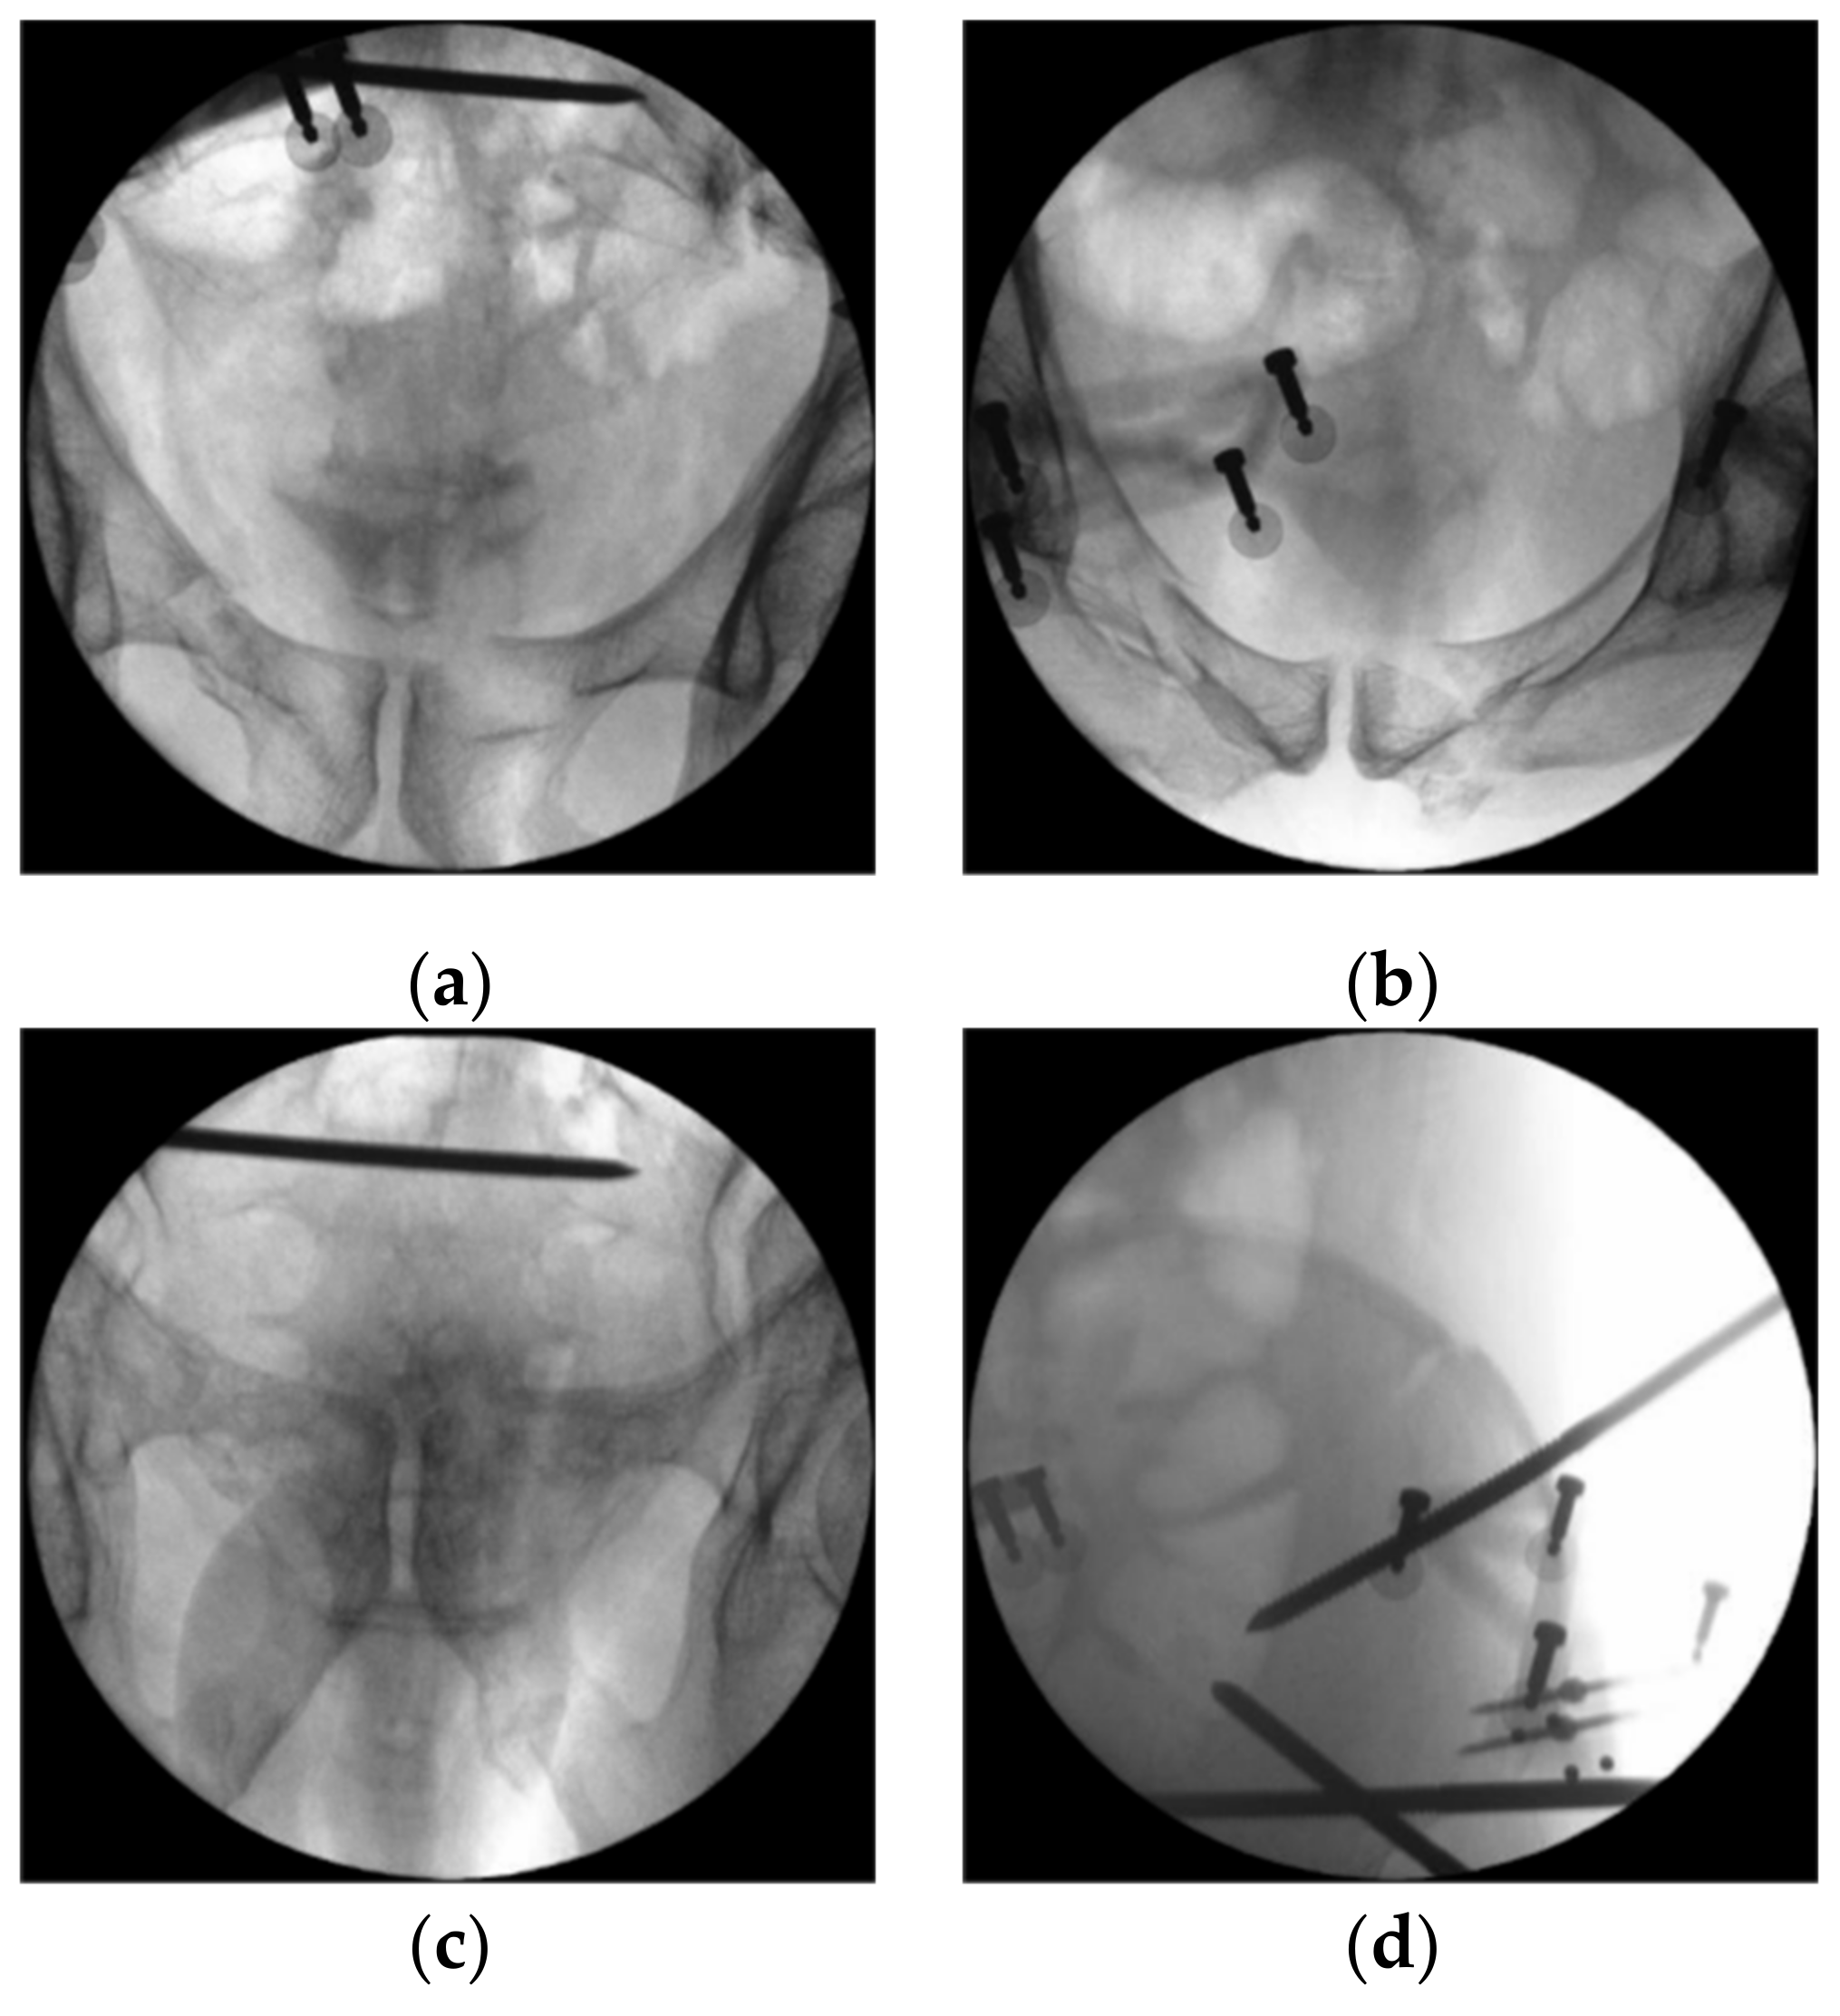

2. Case Report